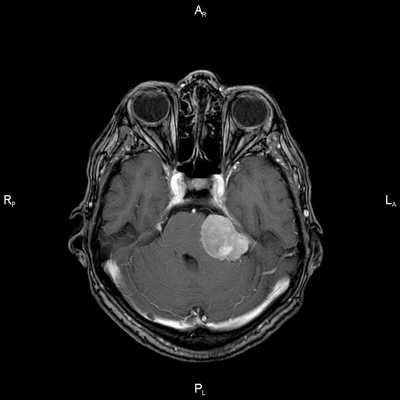

Пациент Р. 62 лет

Проблема: жалобы на частые головные боли, снижение слуха (левое ухо), а также шум в ушах (больше слева). Пациент был направлен на МРТ головного мозга в ЦМРТ с целью уточнения диагноза.

Диагноз: Онкология. Менингиома мосто-мозжечкового угла

Врач ЦМРТ

При МРТ головного мозга в левом мосто-мозжечковом углу определялось больших размеров округлой формы внемозговое патологическое образование, с четкими ровными контурами, широким основанием, прилежащее к твердой мозговой оболочке. После внутривенного контрастирования отмечалось равномерное, выраженное усиление интенсивности МР-сигнала от вышеописанного образования, а также твердой мозговой оболочки. Пациенту был поставлен диагноз (менингиома левого мосто-мозжечкового угла).